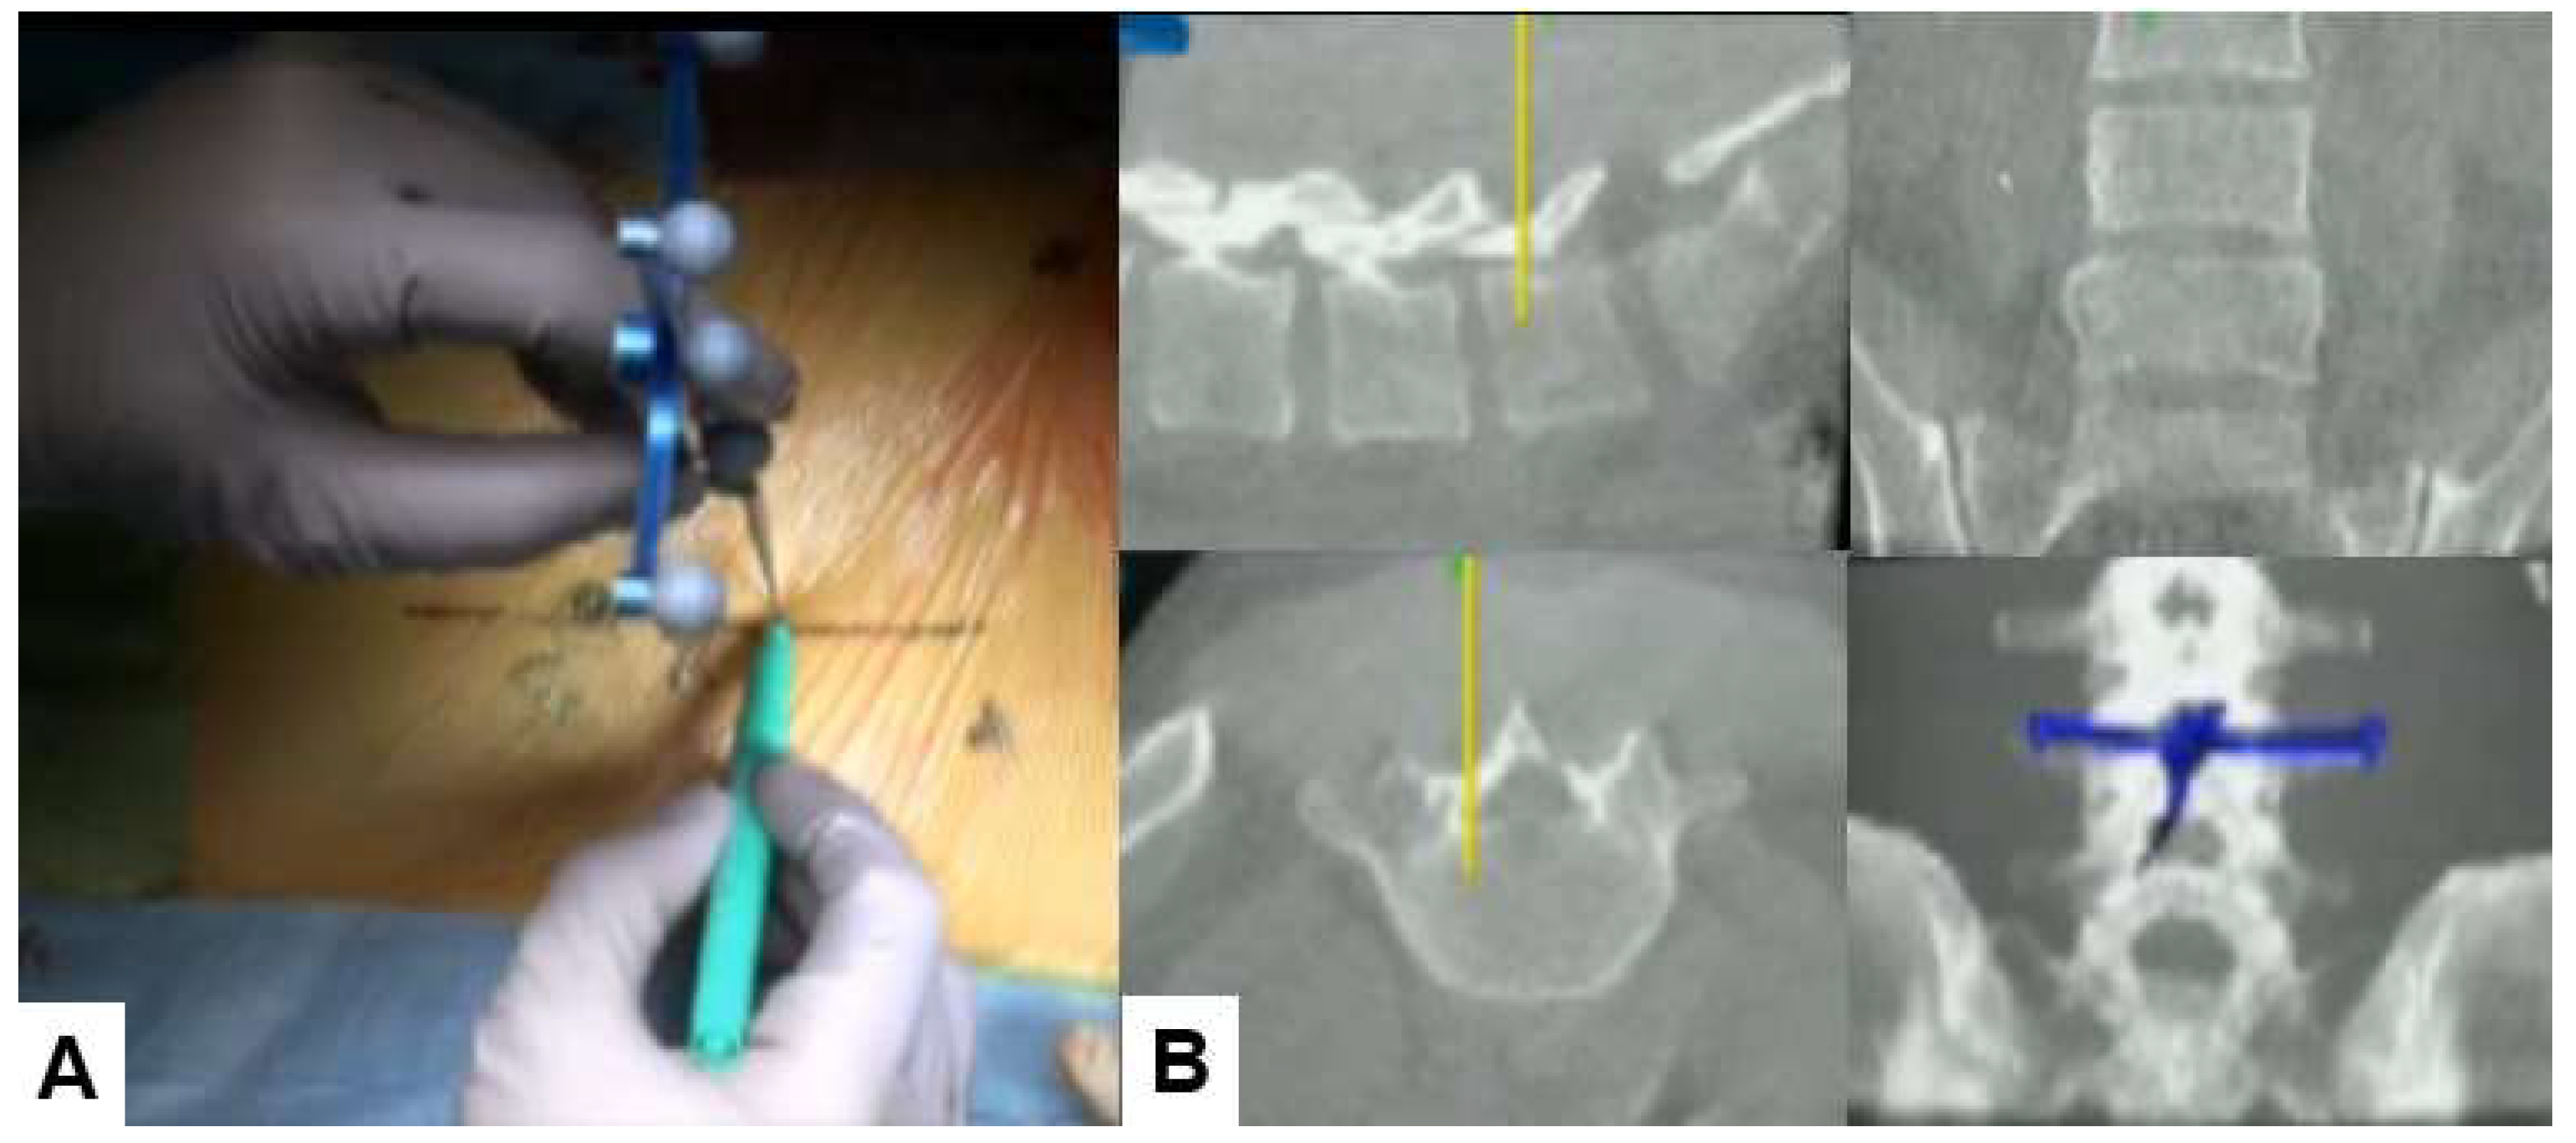

Patient is in a prone position on a full carbon operating table under general anesthesia. We utinely perform neuromonitoring using a multi-modality intraoperative monitoring system. For a muscle of which the innervated nerve is decompressed adequately, the amplitude of the MCV usually increases. A navigation reference frame (RF) is placed percutaneously into the contralateral side sacroiliac joint. Then intraoperative CT scan images with a mobile CT scanner (O-arm) is obtained. After that every instrument is registered such as the navigated pointer, dilater and high-speed burr (Figure 3).

With the help of a navigated pointer, two longitudibnal 6-7mm skin incision are marked. First line is medial pedicle line of L4-L5. One skin incision is for surgical instruments (just paralle to upper endoplate of L5, Figure 4) and the other is for endoscopy (2 cm cranial of the first one). The working space at intelaminar spce is made by navigated first dilater. Then the endoscpy is inserted on the left side and the monopolar on the right side. The soft tissue around interlaminar space is coagulated with the monopolar and lateral edge of L5 lamina is resected with the navigated high speed burr, the ultrasonic bone cutter, and and Kerrison rongeurs. Before using the navigated instruments, the surgeon should check the accuracy of navigation because sometimes the reference frame shifts.. During bony resection, the navigated probe is used to confirm the location (Figure 5).

Figure 4. Skin incision, A: Intraoperative image, B: Navigation monitor.